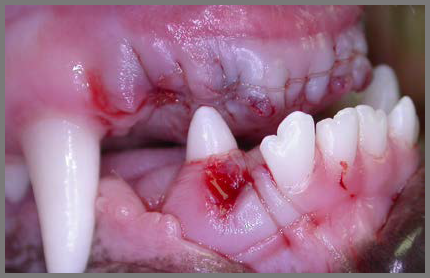

De volgende foto laat een gebit zien, waarvan alle bovenste snijtanden getrokken zijn. Daarnaast is er een tand verwijderd die de hoektand belemmerde. Na zo’n behandeling is het de bedoeling dat pijnlijke kiezen weg zijn en de bek beter sluit. De snijtanden kunnen nu geen pijnlijke groeven meer maken in de onderkant van de bek.